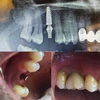

Periimplantitis

Ağız diş ve çene cerrahisi